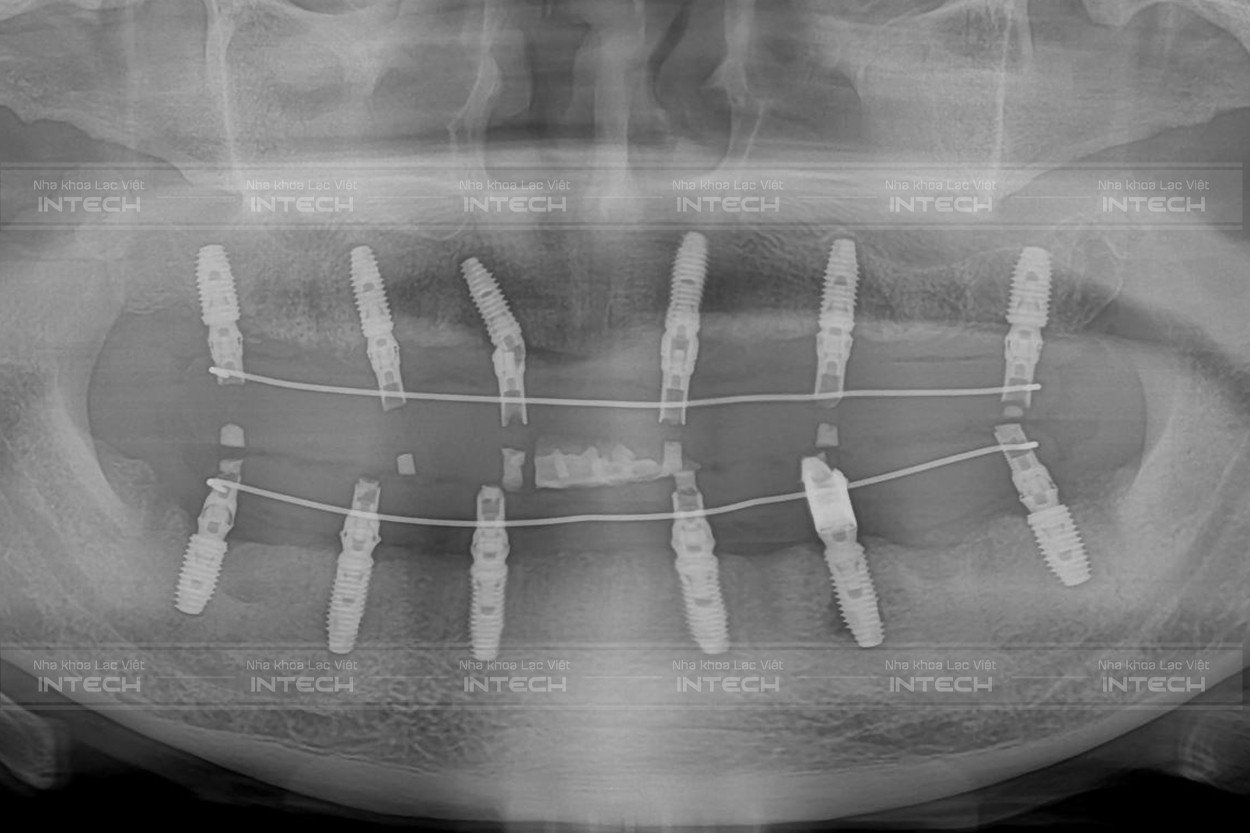

Hình ảnh phim chụp sau cấy ghép implant của chú Hải (Ảnh: Nha khoa Lạc Việt)

Bác sĩ Vũ Đức Duy cho biết quá trình trồng răng implant của chú Hải sẽ diễn ra vô cùng nhanh chóng, không đau, chính xác theo đúng kế hoạch đã đưa ra do được áp dụng công nghệ Safe-Tech độc quyền tại Nha khoa Lạc Việt Intech.